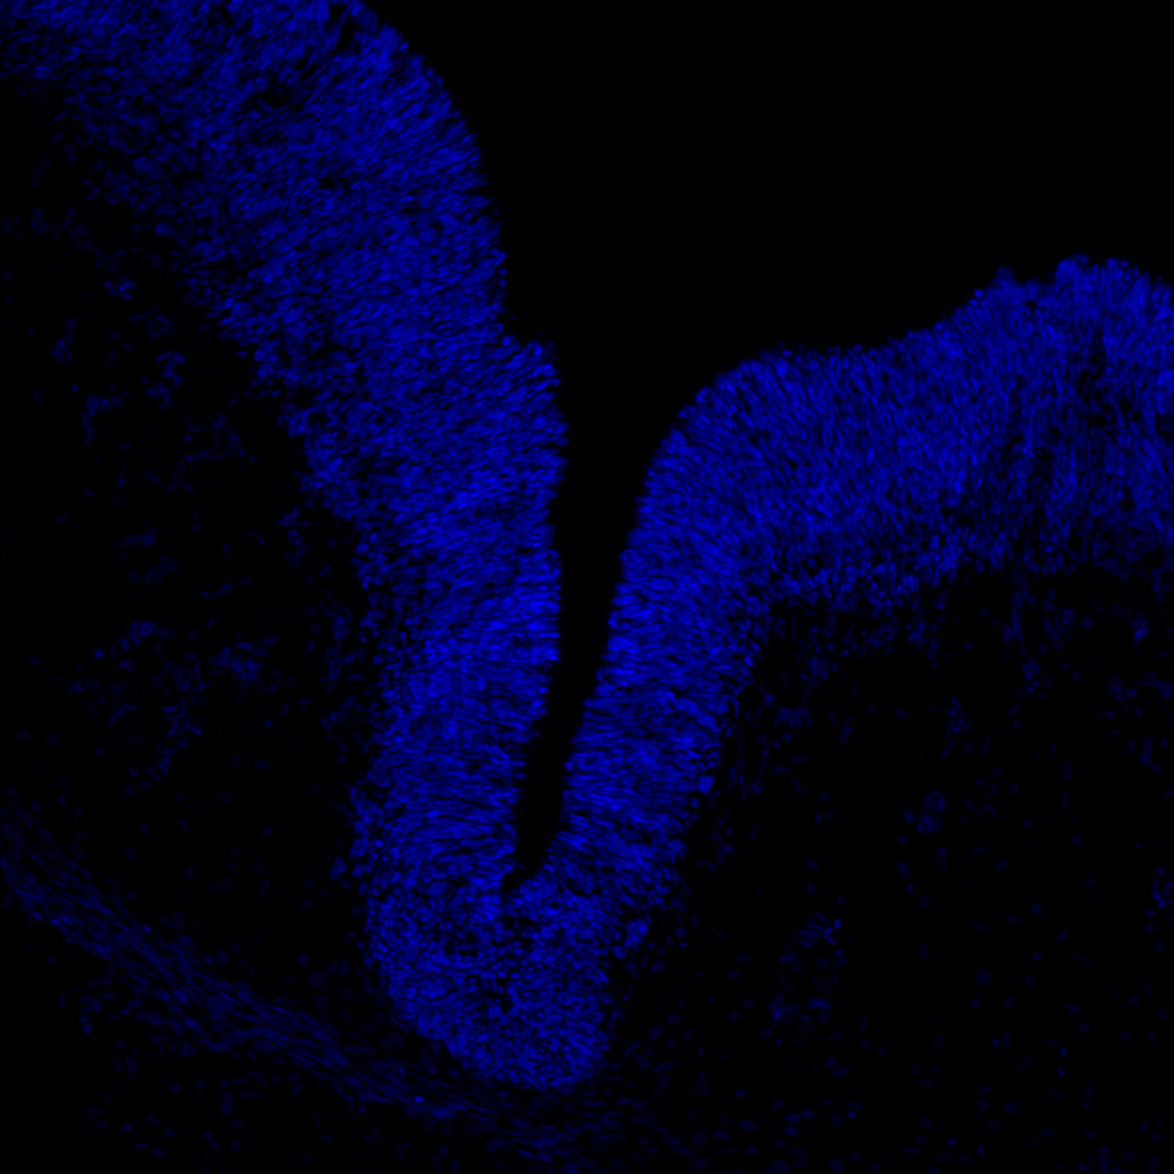

An anatomical analysis of the developing human midbrain from 6 post-conceptional weeks (PCW) to 22 PCW reveals increased tissue complexity, characterized by the emergence of dopaminergic nuclei, as highlighted by immunofluorescence analysis for tyrosine hydroxylase (TH).

11PCW

DAPI

11PCW human midbrain

MAP2

SOX2

Merged